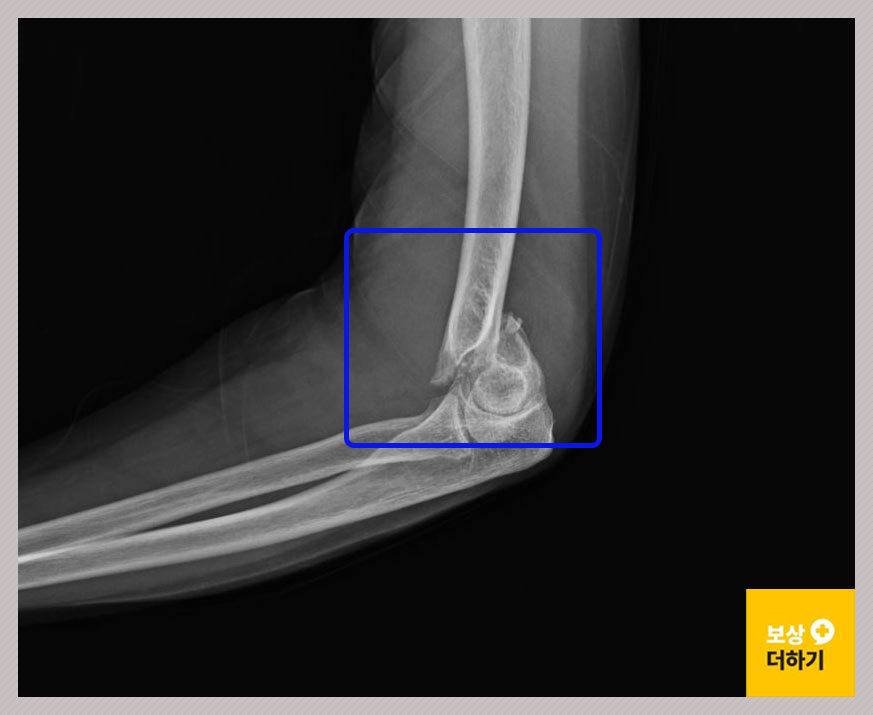

상완골 원위부 (팔꿈치)

상완골은 어깨와 팔꿈치 사이의 뼈입니다. 아랫부분 즉 하단을 상완골 원위부라고 하고, 쉽게 팔꿈치 부위라고 생각하시면 됩니다.

60대 여성인 최 00 님은 길에서 돌부리에 걸려 넘어지는 사고로 다음과 같은 진단을 받으셨어요. 좌측 상완골 원위부 골절 S4230 왼쪽 팔꿈치가 골절된 것이죠.

위 사고로 수술이 진행되었는데요. 금속 고정술을 받고 18일간 입원하셨습니다. 관절 부위는 외상 후 강직이 발생하기 쉽기 때문에 재활치료도 열심히 받으셨습니다.